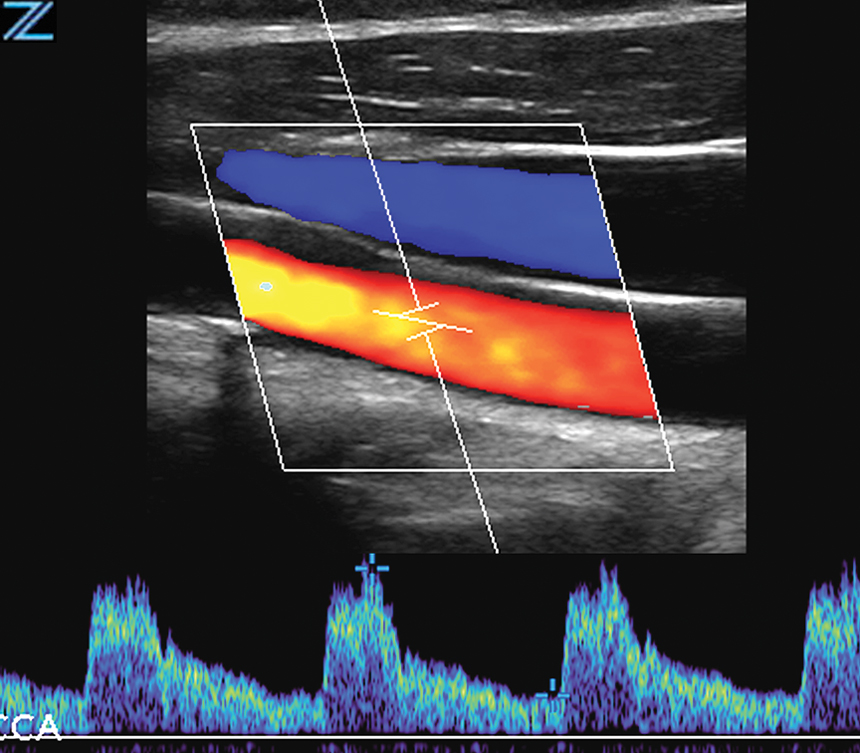

Carotid | L9-3